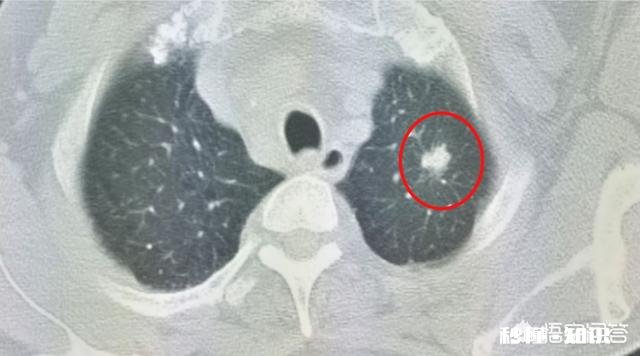

最近遇到两位相似的病人 , 病理都是大细胞神经内分泌癌 , 都发生于左肺上叶,都是接近3厘米的肿瘤,一位已经7年了还好好的,另一位只坚持了不到两年 。

文章插图

这是那位已生存7年的老爷子 , 走起路来呼呼带风 , 说话嗓门很大,一直乐呵呵的 。

乐观的情绪对病人的治疗是有益的 。